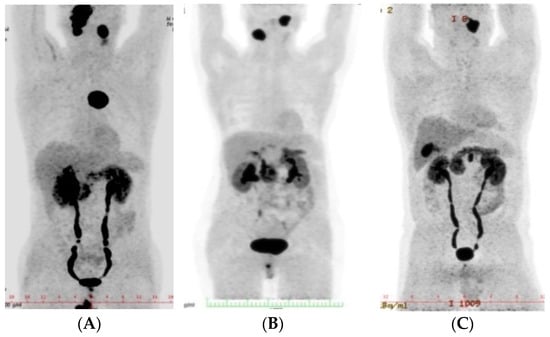

| Patient No. | Age at Diagnosis (Years) | Gender | Genetic Mutation | Syndrome | Type and Localization of HNPGLs | Classification of Tumors | Other PGLs |

|---|---|---|---|---|---|---|---|

| 1 | 34 | M | - | - | Carotid (B) | L: Shamblin III, R: Shamblin II | - |

| 2 | 36 | M | SDHD: c.1A > G (p.Met1Val) | PGL1 | Carotid (B) Vagal (B) Jugular (R) | Shamblin III | Anterior |

| Fisch C | Mediastinum | ||||||

| Fisch C4 Di2 | |||||||

| 3 | 43 | F | SDHD: c.112C > T,p.R38 | PGL1 | Carotid (R) Vagal (L) | Shamblin II | Retroperiotoneal |

| Fisch A | |||||||

| 4 | 47 | M | SDHB: c.287G > A (p.Gly96Asp) | PGL4 | Vagal (L) Jugular (L) | Fisch A | Retroperiotoneal |

| Fisch C1 | |||||||

| 5 | 51 | M | - | - | Carotid (B) Jugular (B) Tympanic (L) | Shamblin II | - |

| Fisch A1 | |||||||

| 6 | 57 | F | SDHD: c.53–2A > G | PGL1 | Vagal (R) Jugular (R) | Fisch A | - |

| Fisch C1 |